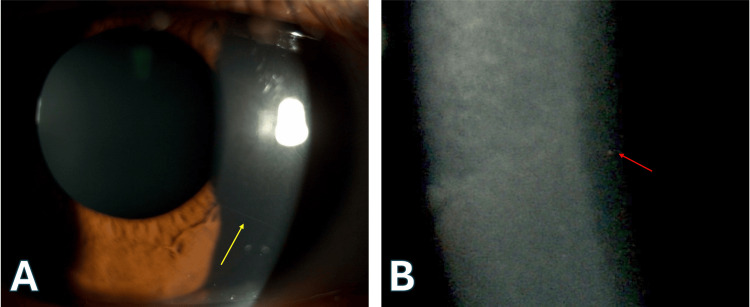

眼科檢查顯示雙眼視力和眼壓正常。然而,角膜檢查顯示明顯的角膜神經(jīng)(圖2A)和深層基質(zhì)點(diǎn)狀改變(圖2B),沒有活動(dòng)性上皮糜爛,提示疾病處于靜止期。此外,雙眼均發(fā)現(xiàn)色素性內(nèi)皮沉積物。眼瞼檢查顯示位置正常,無瞼外翻或兔眼,但眼周皮膚干燥。淚膜評估顯示淚膜破裂時(shí)間縮短,表明眼表干燥。

圖2. 明顯的角膜神經(jīng)和點(diǎn)狀深層基質(zhì)混濁。

A:明顯的角膜神經(jīng)(黃色箭頭)。B:點(diǎn)狀深層基質(zhì)混濁(紅色箭頭)。